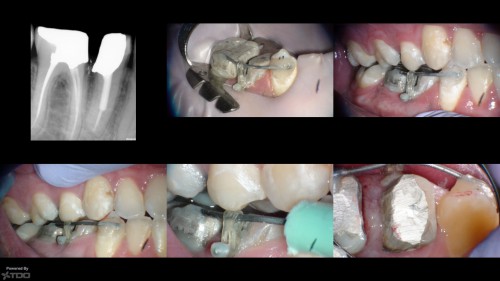

#3 Pulpitis. Er. RCT

#3 Er. RCT. Pulpitis probably following a recent amalgam close to the distal pulp horn. […]